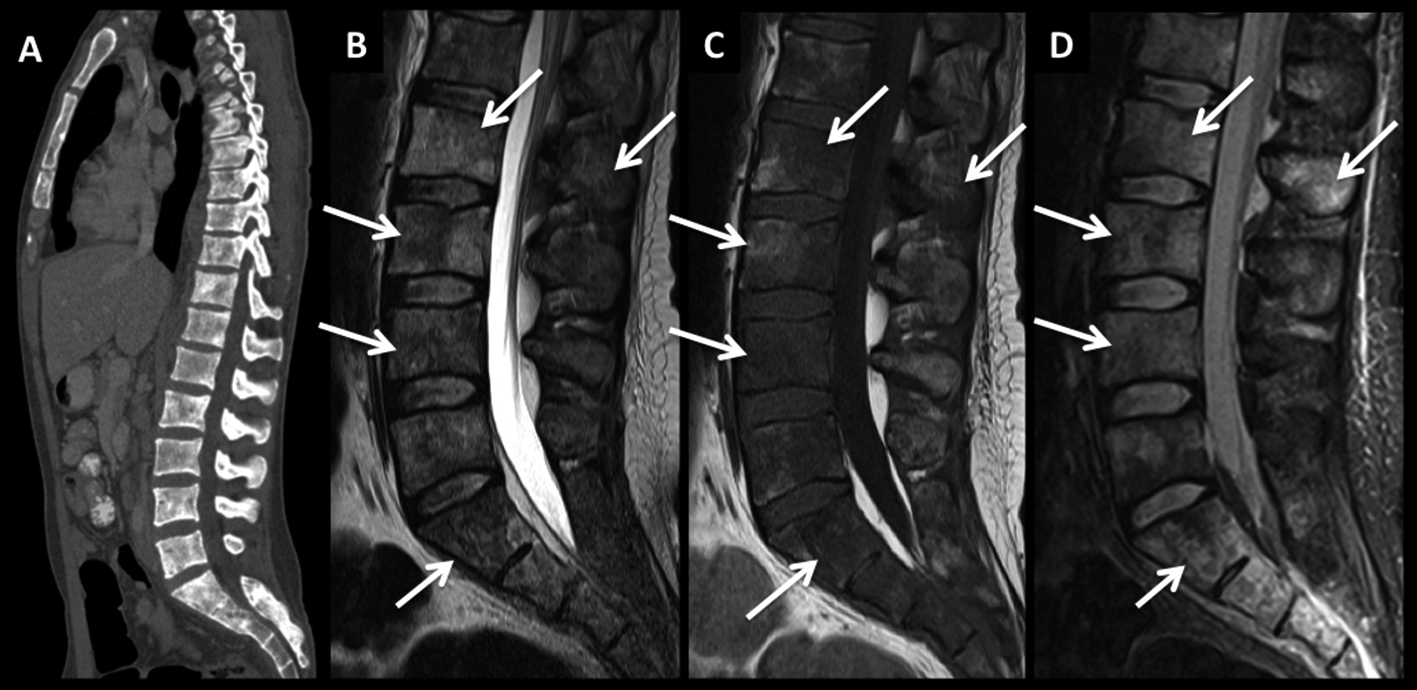

Figura 3

LNH, lesión ósea única, compromiso secundario. (cont)

En el paciente se observa un patrón de lesiones múltiples de sustitución con un patrón infiltrativo. En la TC plano sagital (A) se observa un aumento difuso, parcheado de la densidad, sin aplastamientos vertebrales.

En RM, secuencia T2 sagital (B) las lesiones están mal definidas con alta señal, hipointensas en secuencia T1 (C) y edema en secuencia STIR (D).

Este patrón, menos frecuente, tiene diferentes diagnósticos diferenciales, sobre todo con el mieloma múltiple.